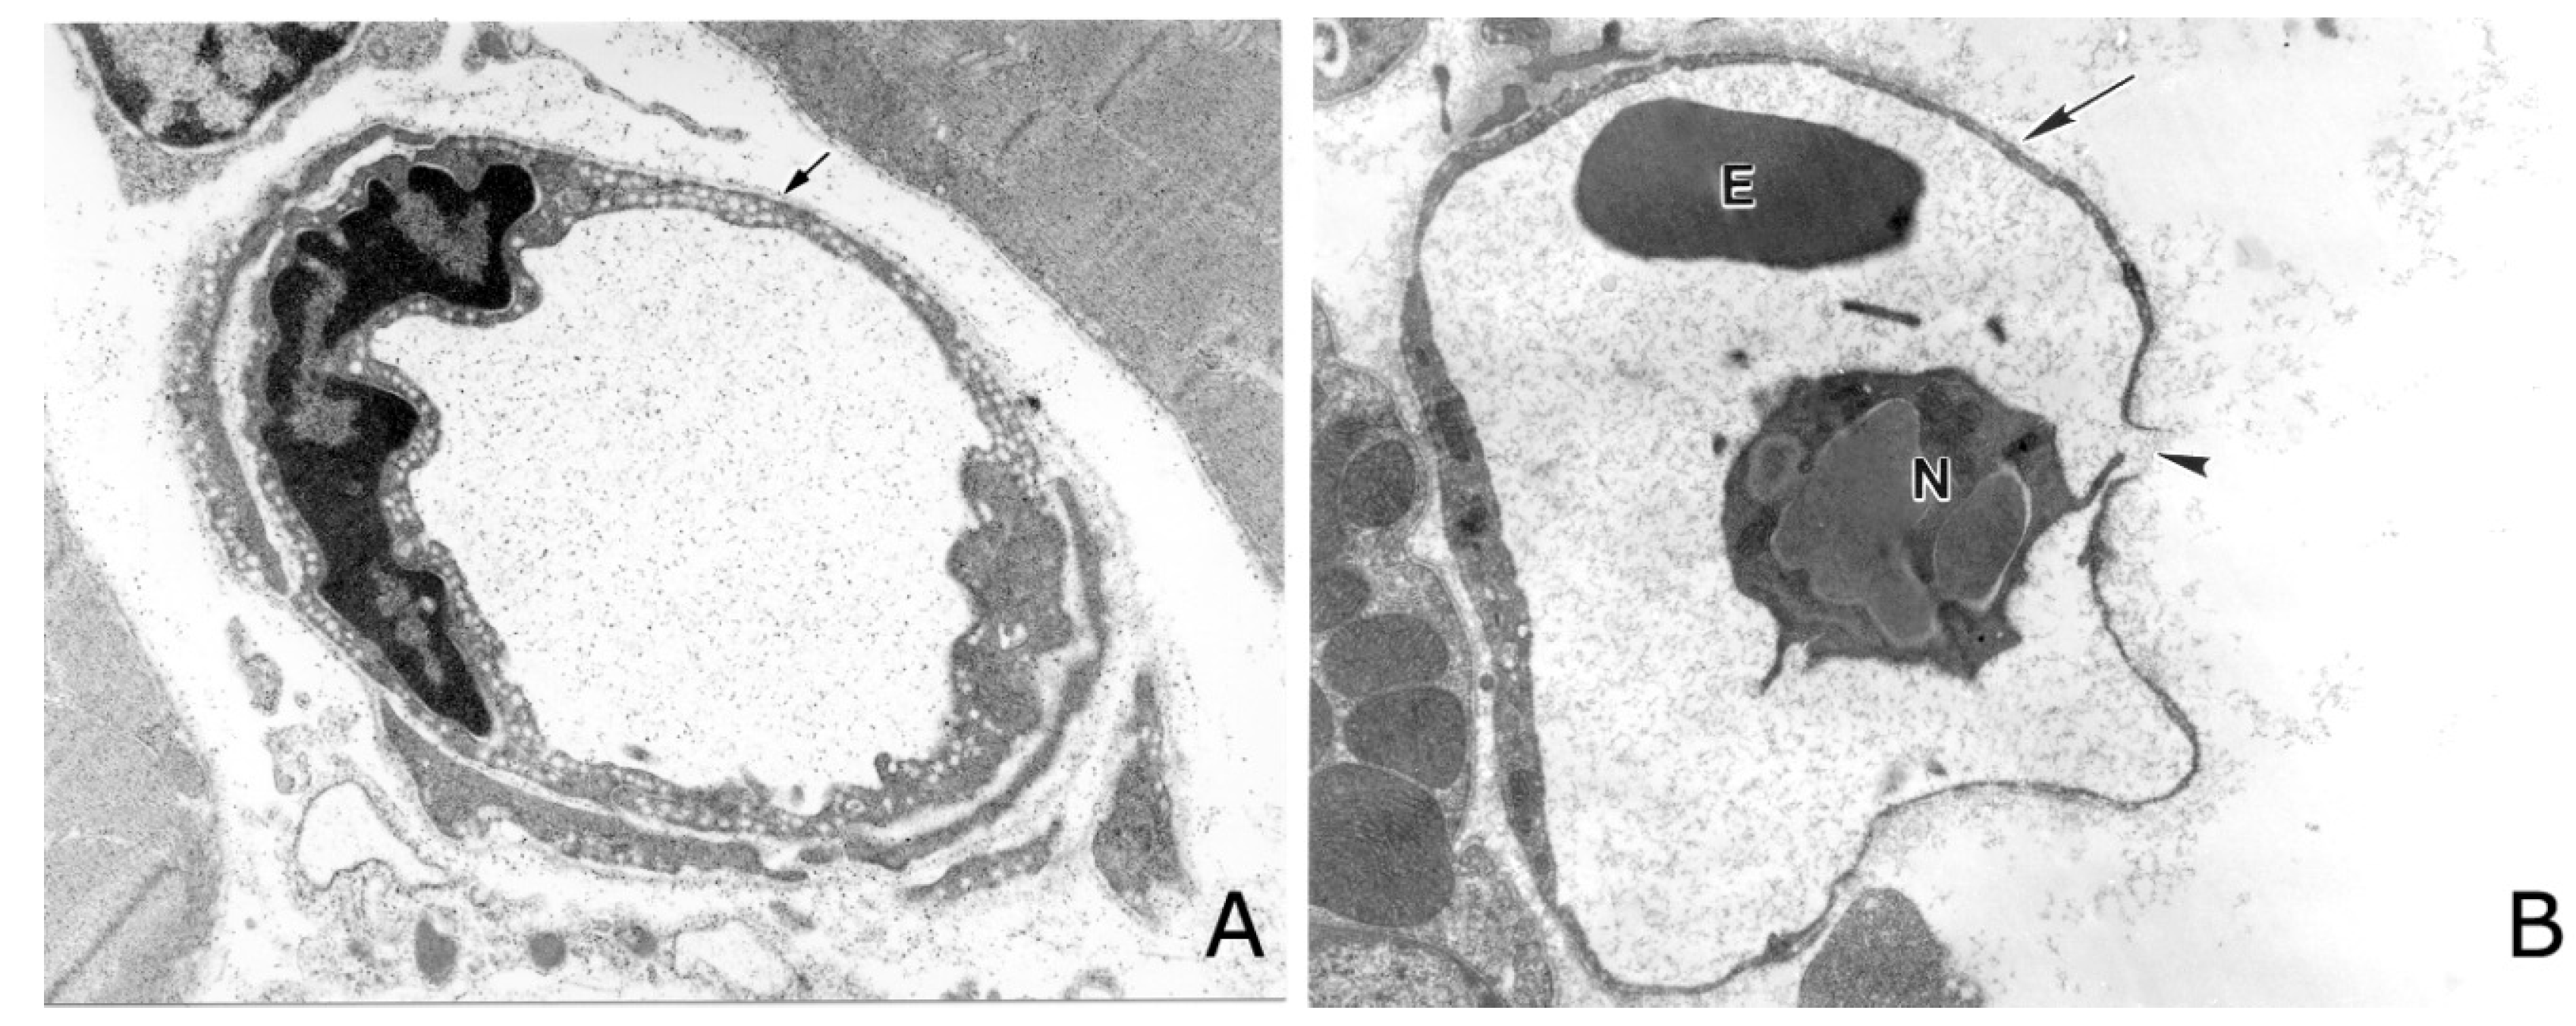

- Ownby, C.L.; Kainer, R.A.; Tu, A.T. Pathogenesis of hemorrhage induced by rattlesnake venom. An electron microscopic study. Am. J. Pathol. 1974, 76, 401–414. [Google Scholar] [PubMed]

- Ownby, C.L.; Bjarnason, J.B.; Tu, A.T. Hemorrhagic toxins from rattlesnake (Crotalus atrox) venom. Pathogenesis of hemorrhage induced by three purified toxins. Am. J. Pathol. 1978, 93, 201–218. [Google Scholar] [PubMed]

- Moreira, L.; Borkow, G.; Ovadia, M.; Gutiérrez, J.M. Pathological changes induced by BaH1, a hemorrhagic proteinase isolated from Bothrops asper (Terciopelo) snake venom, on mouse capillary blood vessels. Toxicon 1994, 32, 976–987. [Google Scholar] [CrossRef]

- Escalante, T.; Rucavado, A.; Fox, J.W.; Gutiérrez, J.M. Key events in microvascular damage induced by snake venom hemorrhagic metalloproteinases. J. Proteom. 2011, 74, 1781–1794. [Google Scholar] [CrossRef] [PubMed]